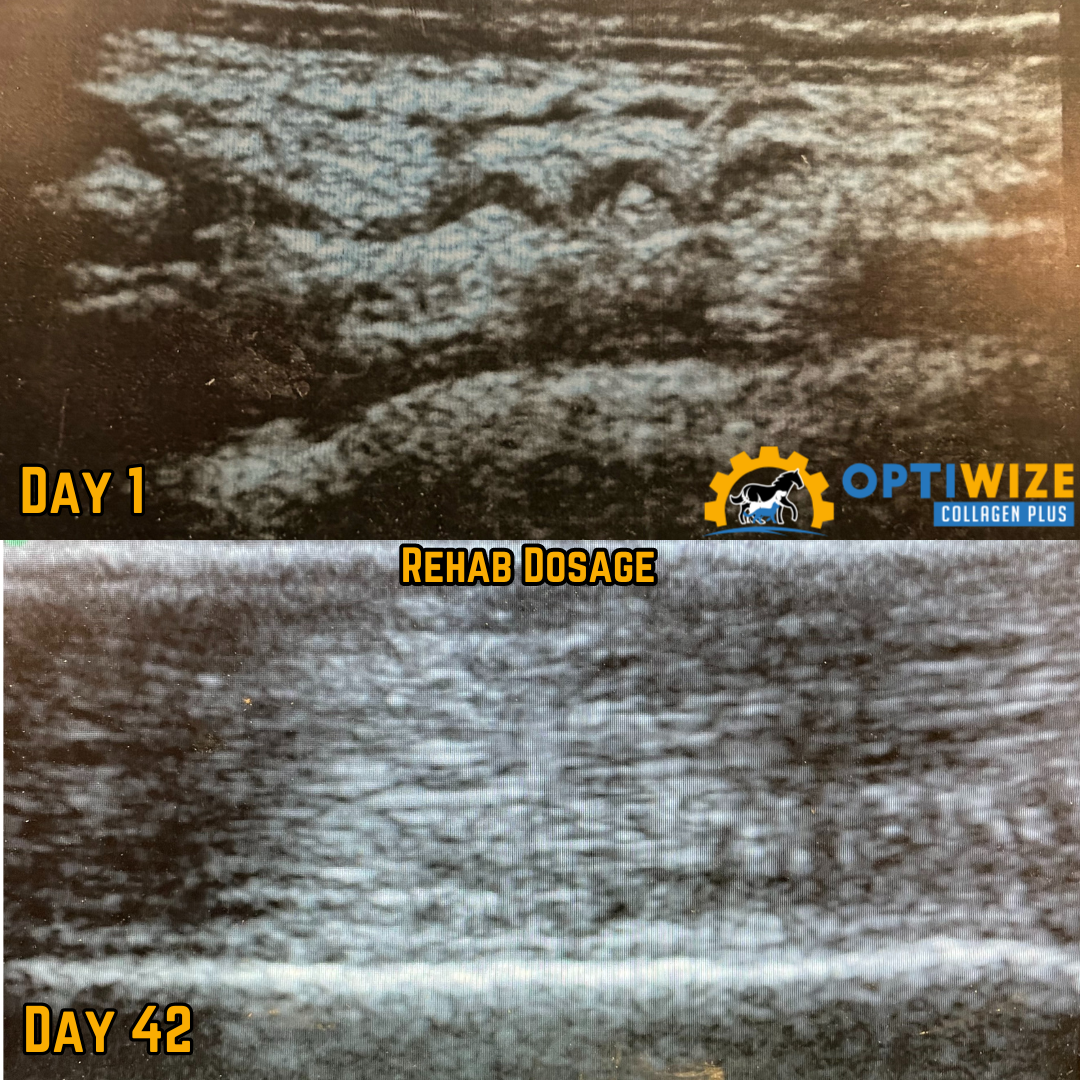

• OptiWize rehab dose: Day 1 to 42.